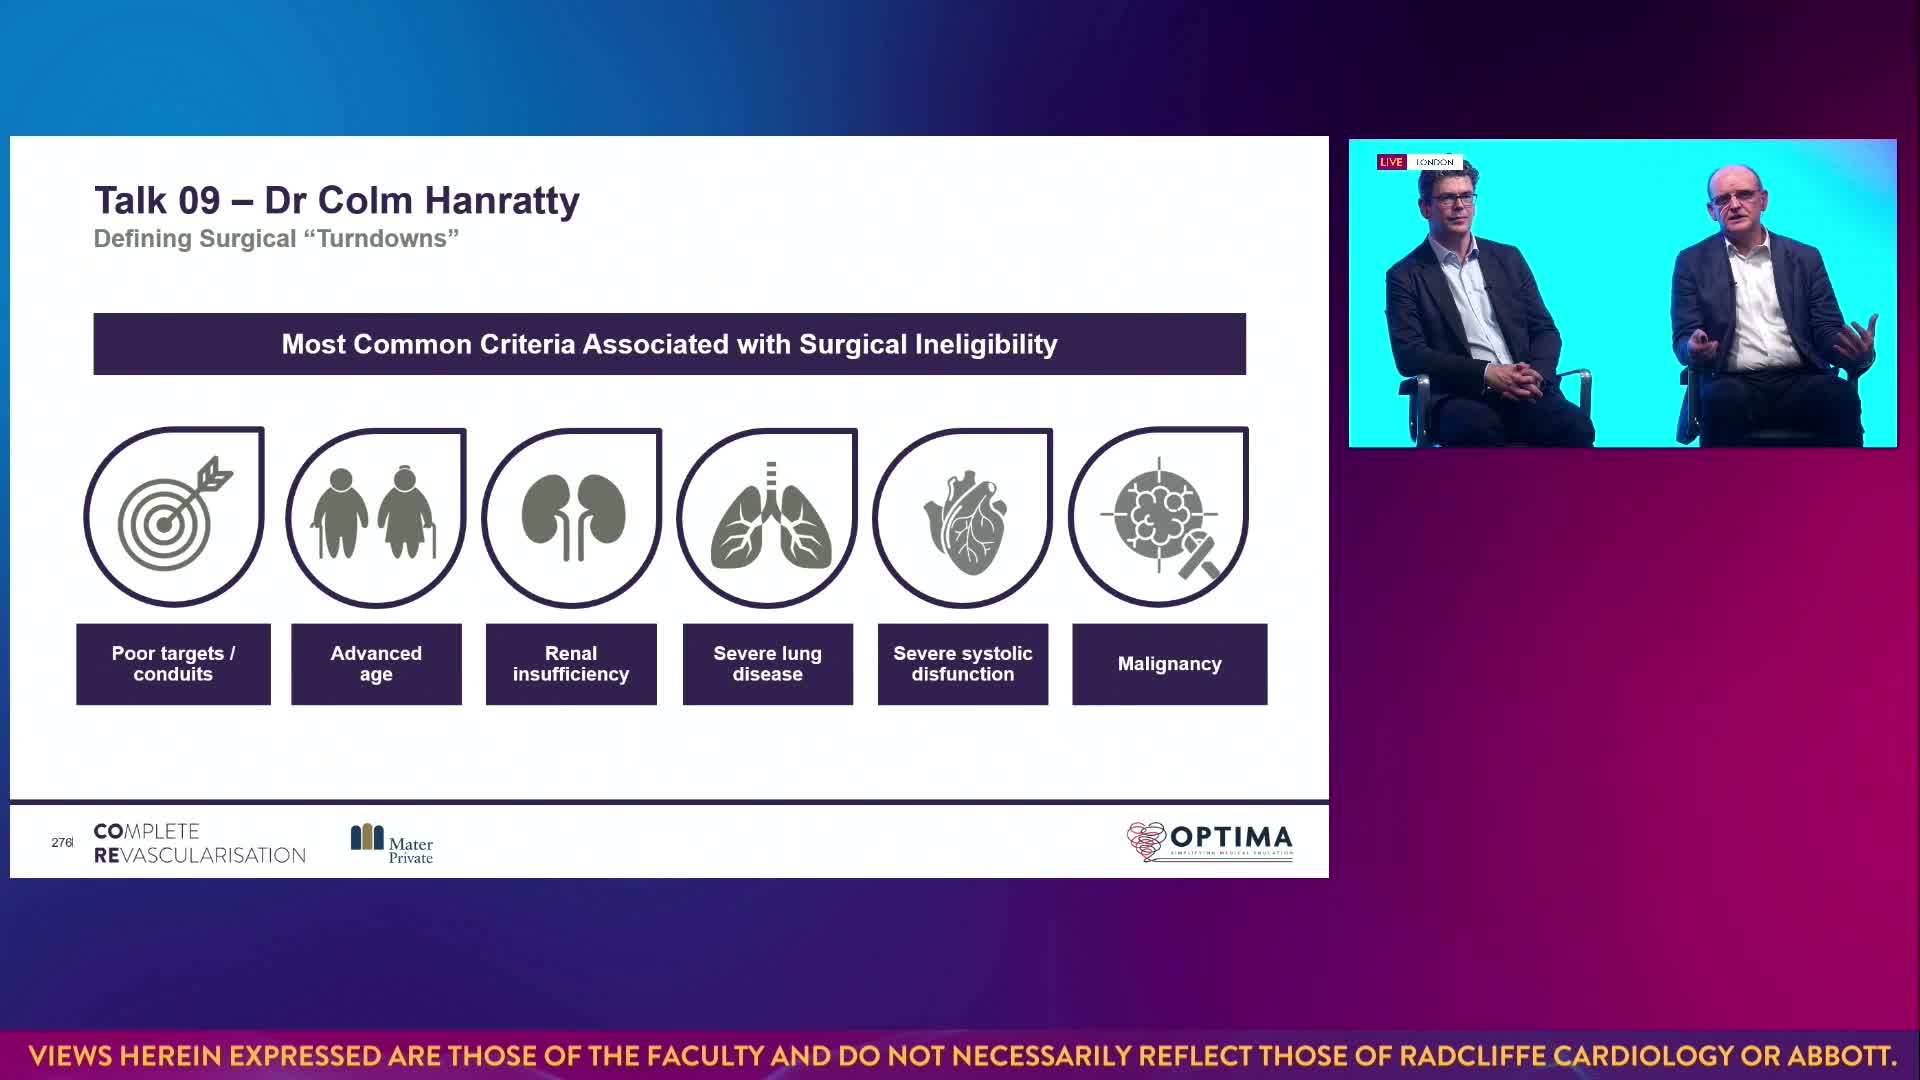

Session 4: High-risk and complex – too tough to treat?

Colm Hanratty

A consultant cardiologist at Mater Private Hospital, Dublin, Ireland. Features in 20 videos on...

Read More

A consultant cardiologist at Mater Private Hospital, Dublin, Ireland. Features in 20 videos on Wondr Medical. Colm Hanratty generally speaks on Fractional Flow Reserve (FFR), Intravascular Ultrasound (IVUS), Chronic Total Occlusion (CTO), Calcium Scoring, and Stable Coronary Artery Disease (CAD).